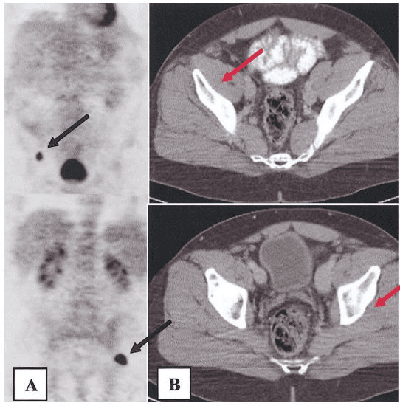

The application of machine learning to radiological images is an increasingly active research area that is expected to grow in the next five to ten years. Recent advances in machine learning have the potential to recognize and classify complex patterns from different radiological imaging modalities such as x-rays, computed tomography, magnetic resonance imaging and positron emission tomography imaging. In many applications, machine learning based systems have shown comparable performance to human decision-making. The applications of machine learning are the key ingredients of future clinical decision making and monitoring systems. This review covers the fundamental concepts behind various machine learning techniques and their applications in several radiological imaging areas, such as medical image segmentation, brain function studies and neurological disease diagnosis, as well as computer-aided systems, image registration, and content-based image retrieval systems. Synchronistically, we will briefly discuss current challenges and future directions regarding the application of machine learning in radiological imaging. By giving insight on how take advantage of machine learning powered applications, we expect that clinicians can prevent and diagnose diseases more accurately and efficiently.